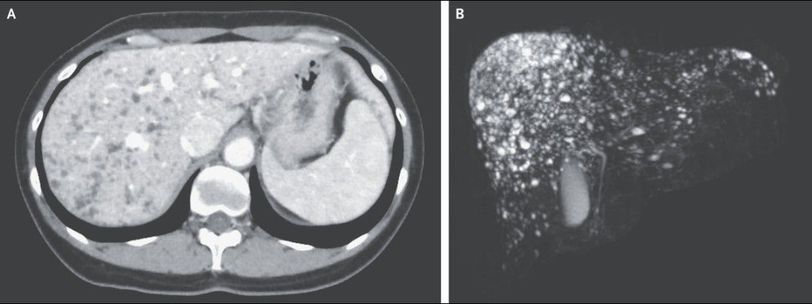

A 45-year-old woman was referred to the outpatient clinic after multiple hepatic lesions were incidentally noted on imaging. She had no related symptoms, and the physical examination was normal. Laboratory tests showed no liver dysfunction, with normal levels of alanine aminotransferase, alkaline phosphatase, and bilirubin and a normal international normalized ratio. Enhanced computed tomography of the abdomen showed multiple small, hypodense, nonenhancing nodules throughout the liver (Panel A). Magnetic resonance imaging with cholangiopancreatography revealed multiple small, T2-weighted, hyperintense cystic nodules in the liver, with no biliary duct communication, creating a “starry sky” appearance (Panel B). These findings were consistent with biliary hamartomas, benign malformations of the intrahepatic biliary ducts. No specific treatment was initiated, and at a follow-up visit 2 years after presentation, the imaging findings were unchanged.